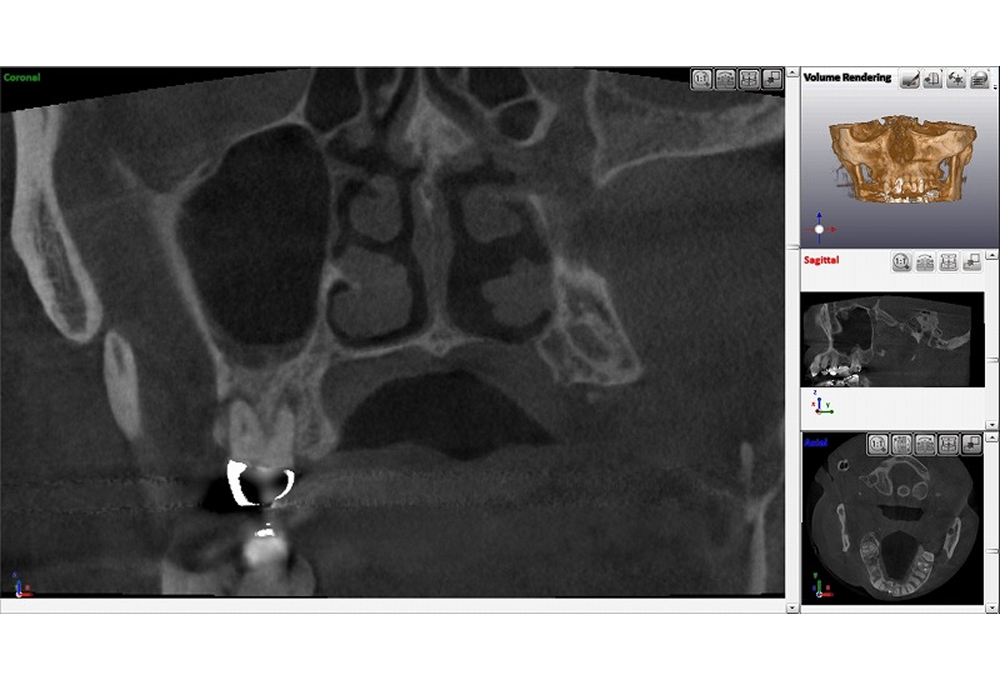

②CTで上顎洞粘膜肥厚 根尖病変確認